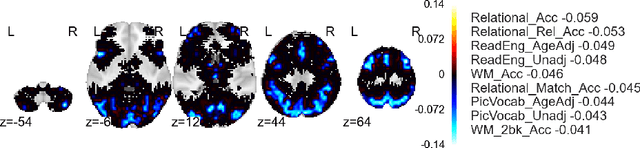

Abstract:Given two sets of variables, derived from a common set of samples, sparse Canonical Correlation Analysis (CCA) seeks linear combinations of a small number of variables in each set, such that the induced canonical variables are maximally correlated. Sparse CCA is NP-hard. We propose a novel combinatorial algorithm for sparse diagonal CCA, i.e., sparse CCA under the additional assumption that variables within each set are standardized and uncorrelated. Our algorithm operates on a low rank approximation of the input data and its computational complexity scales linearly with the number of input variables. It is simple to implement, and parallelizable. In contrast to most existing approaches, our algorithm administers precise control on the sparsity of the extracted canonical vectors, and comes with theoretical data-dependent global approximation guarantees, that hinge on the spectrum of the input data. Finally, it can be straightforwardly adapted to other constrained variants of CCA enforcing structure beyond sparsity. We empirically evaluate the proposed scheme and apply it on a real neuroimaging dataset to investigate associations between brain activity and behavior measurements.